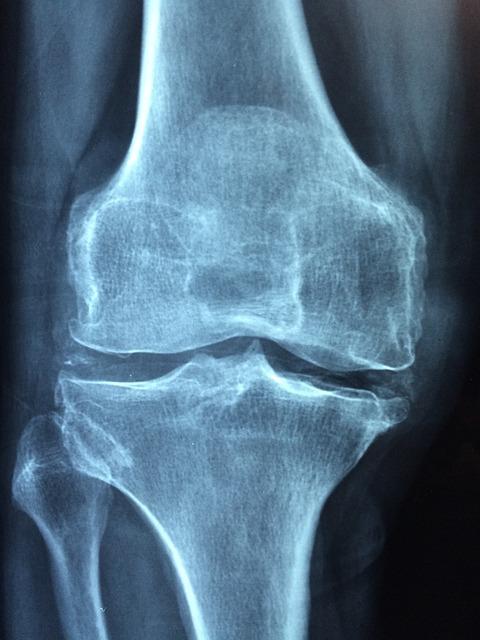

Running has often been scrutinized for its potential effects on knee health, sparking debates and studies around the globe. However, the impact of running on knees isn’t as straightforward as it might seem. Studies suggest that moderate running can actually be beneficial for knee joints, promoting cartilage health and improving joint function. This is due to the increased blood flow and nutrients that help maintain the cartilage, which acts as a cushion between bones. Yet, it’s crucial to consider the nuances of individual health conditions and running habits.

Ultimately, the relationship between running and knee health is complex, shaped by a variety of factors that can either contribute to or protect against knee damage. For those concerned about knee health, incorporating strength training and flexibility exercises can further support joint stability and function.